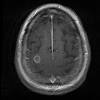

Man coughs up part of lung while being treated for heart failure A 36-year-old California man who was admitted to the intensive care unit with chronic heart failure was coughing so severely that he hacked up an intact cast of the right bronchial tree.

6-inch blood clot coughed up by patient The New England Journal of Medicine tweeted a picture of a 6-inch blood clot coughed up in one piece by a patient Dec. 5 as part of a photo series of medical abnormalities, according to The Atlantic.

Man Coughed Up Rare Blood Clot That Is The Exact Shape Of Lung Passage Doctors are bewildered as to how an extraordinarily shaped blood clot came out of a patient. On Monday, the New England Journal of Medicine tweeted a startling picture as part of its "Images in Clinical Medicine" photo series, which features photos of ...

Man coughs up bizarre blood clot shaped exactly like part of a lung A mysterious and somewhat gross photo of a man's blood clot is getting a lot of attention after the New England Journal of Medicine shared it on Twitter.